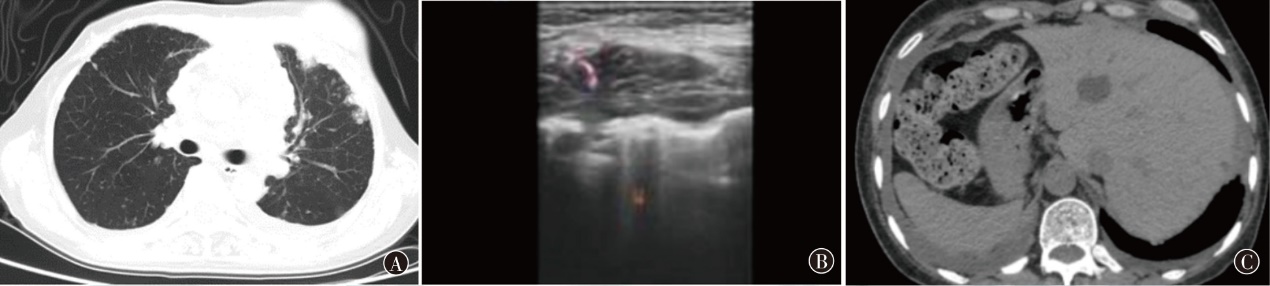

戈沙妥珠单抗于2022年6月正式被国家药品监督管理局批准上市,作为作用于Trop-2靶点的抗体偶联药物,为晚期三阴性乳腺癌患者带来了新的治疗选择。现报道1例晚期三阴性乳腺癌患者在病情出现进展时使用戈沙妥珠单抗治疗后情况,病情变化达到稳定,患者获益较为明显。